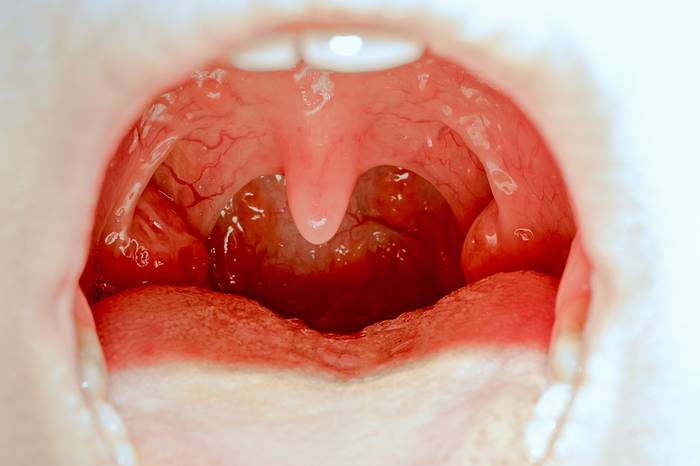

Небные миндалины – это крупные скопления лимфоидной ткани, которые располагаются по бокам глотки между передней и задней небными дужками и являются периферическим органом иммунной системы. Как составляющие иммунной системы, они защищают организм от болезнетворных микробов, проникающих из окружающей среды с воздухом или пищей путем выработки специфических и неспецифических факторов защиты (антител, лизоцима, лактоферина и пр).

Признаки лакунарного и фолликулярного тонзиллитов (гнойная ангина)

Лакунарный и фолликулярный тонзиллит являются гнойными видами ангины, они развиваются при бактериальных инфекциях.

- отек миндалин;

- гиперемия миндалин;

- при фолликулярной форме на миндалинах имеются гнойные фолликулы – округлые образования до 5мм в диаметре, бело-желтого цвета;

- при лакунарной форме на миндалинах имеются скопления гноя в лакунах миндалин, также бело-желтого цвета;

- гнойное отделяемое может покрывать всю поверхность миндалин (гнойный налет).